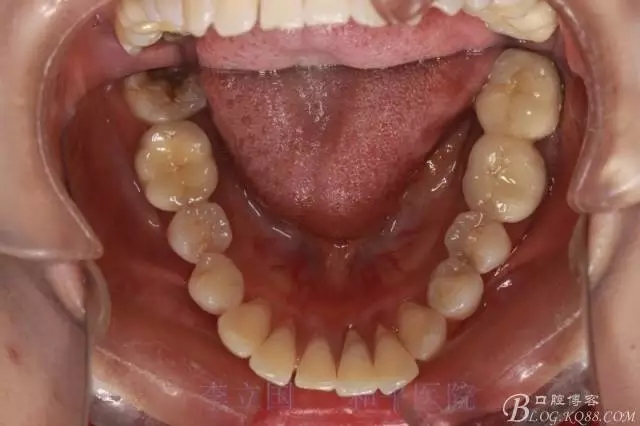

1.拔除14、24、31。

5.回收過程中,上下前牙輕搖椅,防止覆合加深。